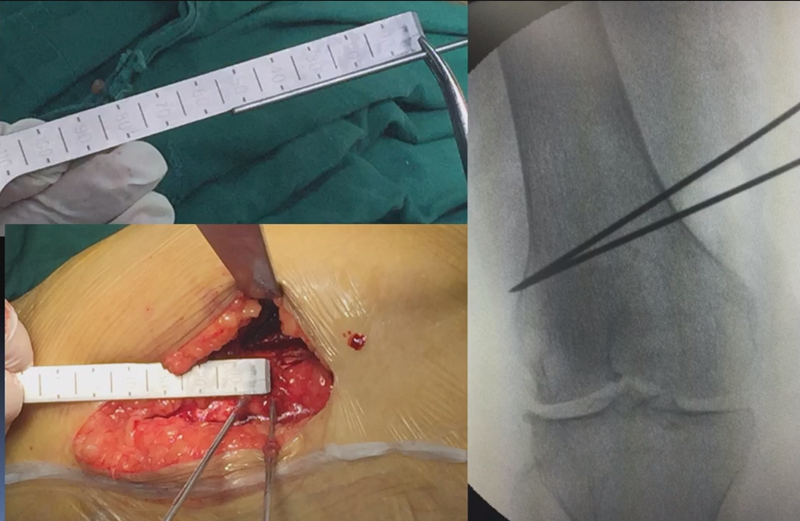

合页点和截骨线已确定好,按照术前计划打入导针,测量截骨深度。

注意,目前临床推荐的DFO要求最好能做双平面截骨,即还要有一条上行截骨线,上行截骨线与水平截骨线夹角大概为95° 左右。这种截骨方式一方面可以增加稳定性,同时也可以减少对上方髌股关节的干扰。

上行截骨时,要保持肢体旋转中立位,前方要有骨撬保护,由内向外完全截开,上行截骨线不存在合页。

水平截骨时,同样放肢体中立位,后侧放一把骨撬保护后方重要结构。

截骨过程中,不要求一次截骨到位,把合页深度全部截到,可以留最后一点,用钻头由前向后打出一排筛孔来,把合页端弱化,再去做闭合时就不容易折断了。